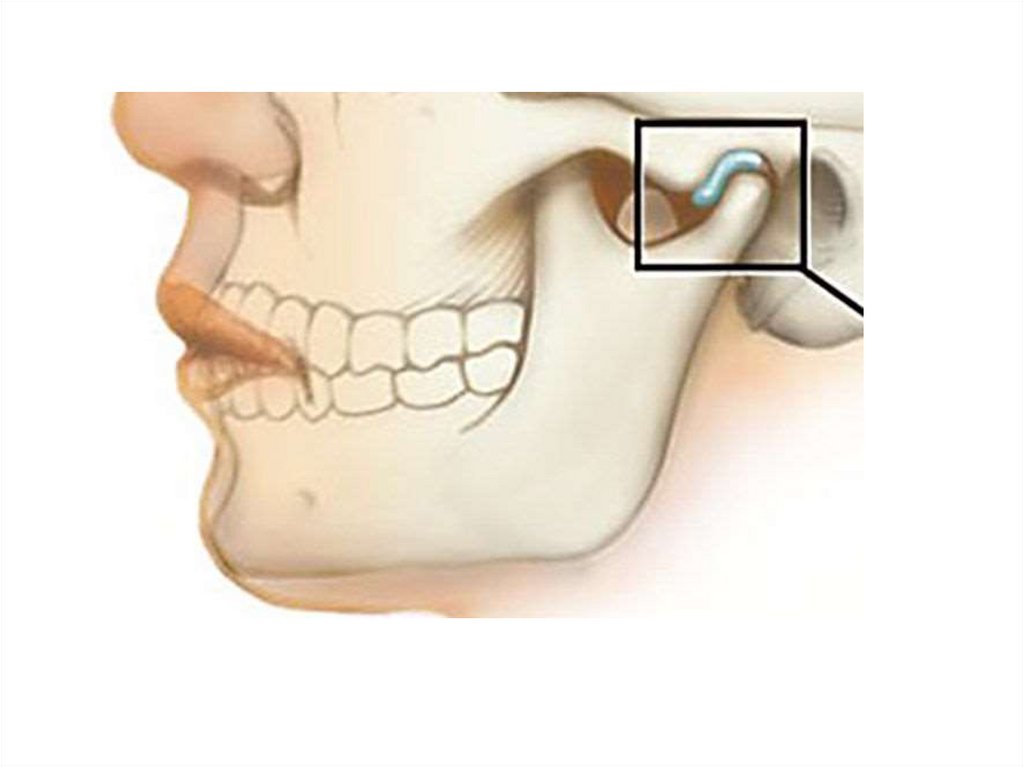

• Принудительный метод базируется на

смещении нижней челюсти назад давлением

руки врача на подбородок. Эта методика

приводит к возникновению форсированного

положения суставных головок и

травмированию дистальных участков диска

ВНЧС, которые не приспособлены к

восприятию такой нагрузки.

• Функциональный метод основан на

использовании функциональных

состояний зубочелюстной системы

(глотание, касание кончиком языка

шарика из воска, который закреплен на

заднем крае верхнего воскового

шаблона) или рефлекторном отведении

нижней челюсти при наложении пальцев

врача на валик в области боковых зубов.

Пациента в это время просят сомкнуть

челюсти, нижняя челюсть при этом

рефлекторно отводится назад.